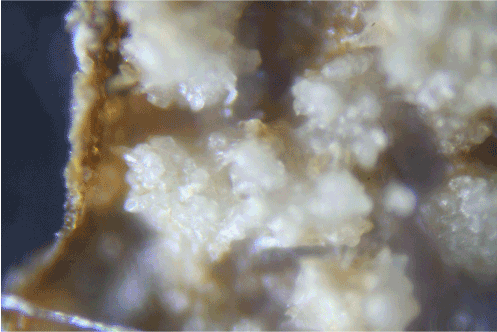

Biopsies from late proliferative stage BDD lesions were examined microscopically for comparison (Figures 5A-5D). Although the scale of filaments was much larger, the BDD filaments (roughly ten times larger) were similar in appearance compared to the specimens observed in Case 1 (Figure 5A, Figure 5B). Filaments were macroscopic, opaque and dirty white in color, ranging in size from less than 0.5 mm in diameter to about 1 mm in diameter. In cross section filaments appeared to originate beneath the stratum corneum (Figure 5C). Longer filaments were close to 1 mm in length. The BDD filaments demonstrated fluorescence under UV light (Figure 5D).

Figure 5D: BDD sample showing coarse fibers with fluorescence under UV lighting (8x magnification).